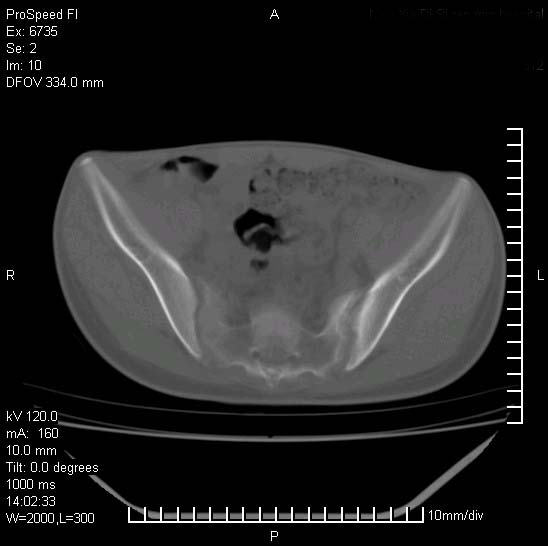

患者自诉胯部疼痛两年余,在当地服用中药,半月前至本院考虑骶髂关节结核,给予抗痨治疗。现发展至右下肢疼痛明显,活动受限,以膝关节处明显,拍膝关节平片无明显异常。

两侧骶骼关节改变,考虑强直性脊炎

左侧骶髂关节面限局性骨破坏,边缘硬化关节腔见钙化物;不出外tb

考虑强直性脊炎,建议查hla-b27

右侧骶髂关节也有类似改变,只是较左侧轻,首先考虑强直性脊柱炎,不除外结核,建议作hla-b27检查。

典型强脊炎改变,髋关节亦有累及

符合强直性脊柱炎表现。